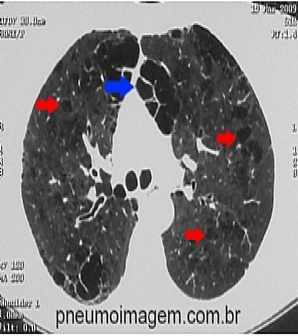

Veja imagens sobre DPOC no PneumoImagem,

clique aqui.